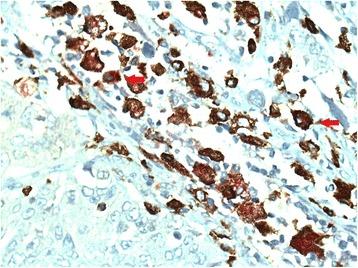

Lung tissue specimens from 80 NSCLC patients who underwent surgical resection for NSCLC (pathological stage I-III) and 16 control group subjects who underwent surgery because of recurrent spontaneous pneumothorax were analyzed. Immunohistochemical double staining of CD68/iNOS (markers for M1 macrophages) and CD68/CD163 (markers for M2 macrophages) was performed and evaluated in a blinded manner. The numbers of M1 and M2 macrophages in tumor islets and stroma were counted manually.

对 80 例接受手术切除 NSCLC(病理分期 I-III 期)的 NSCLC 患者和 16 例因复发性自发性气胸而接受手术的对照组患者的肺组织标本进行分析。采用 CD68/iNOS(M1 巨噬细胞标志物)和 CD68/CD163(M2 巨噬细胞标志物)的免疫组织化学双重染色,并进行盲法评估。手动计数肿瘤胰岛和基质中 M1 和 M2 巨噬细胞的数量。